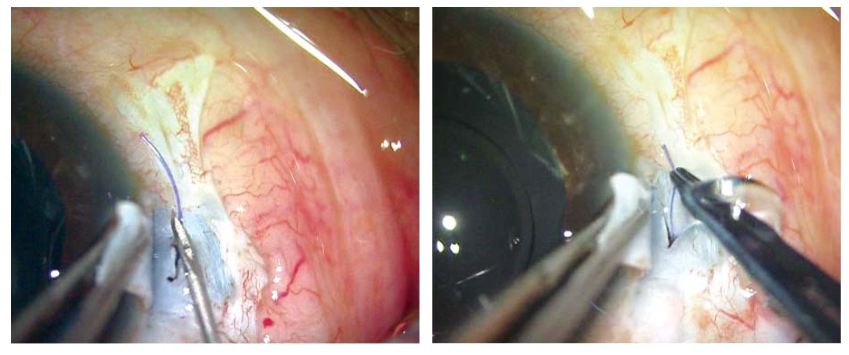

对于有IOL脱位的患者,制作类似上述的板层巩膜瓣,然后用23/25号钳夹住脱位的IOL襻,将其外移并粘在巩膜瓣下(图5A和B)。

图5A和B:使用25G镊子将脱位的IOL襻暴露。